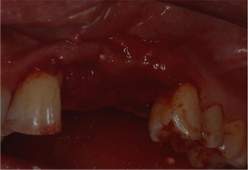

Fig.13

Nelle zone più delicate dell'osso profondo si procede alla osteotomia-osteoplastica con strumenti a mano, meno lesivi, come scalpelli ossei.